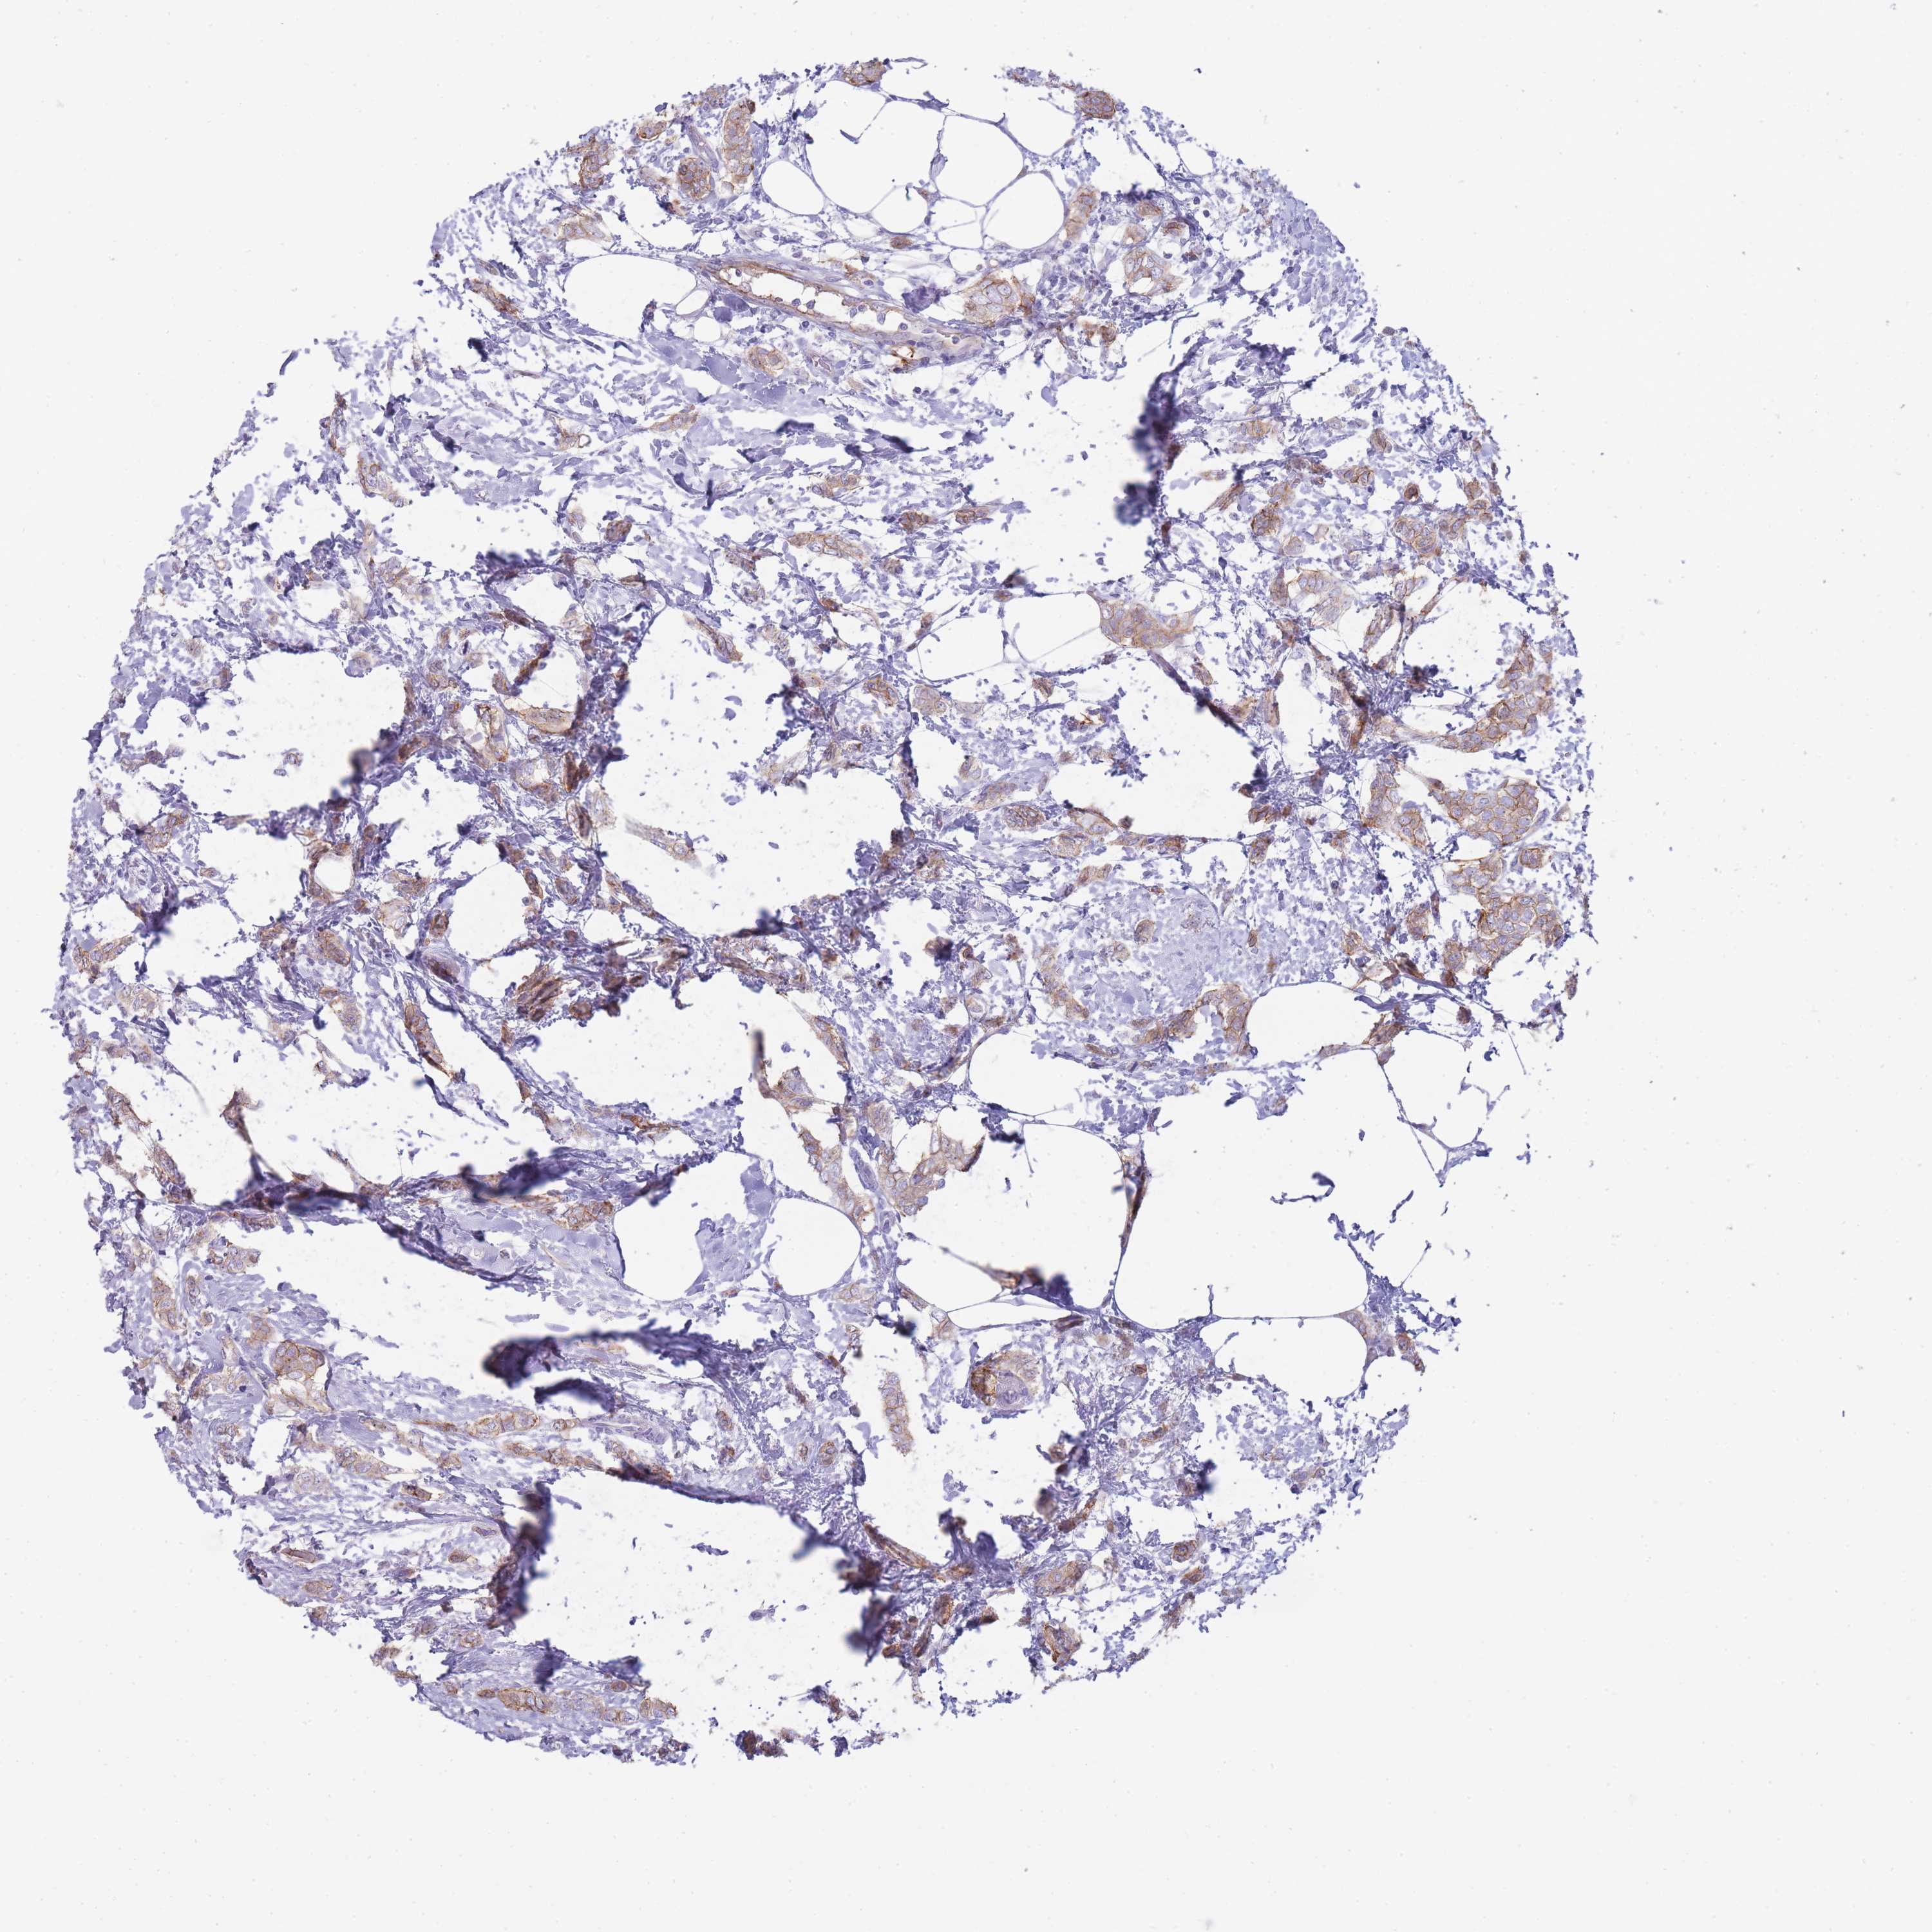

CANCER BREAST CANCER Show tissue menu

BRCA TCGA BRCA VALIDATION PROTEIN EXPRESSION